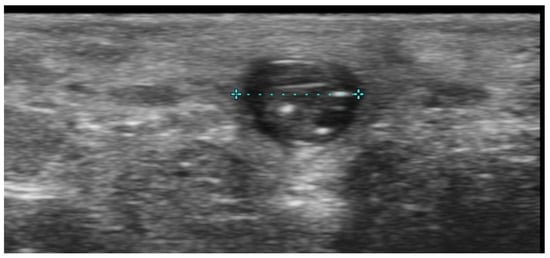

5. Specific Cutaneous Structure and Sites of Skin Disorders